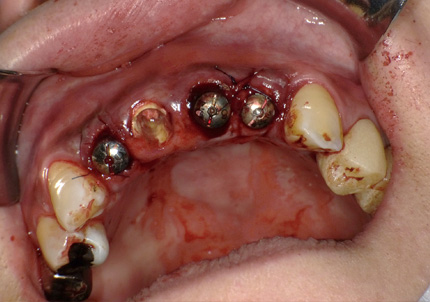

11.舌側歯牙片の抜歯

12.左下6・7番埋入サージカルガイド作製

13.サージカルガイドによる埋入手術(2019年5月)

14.インプラント埋入

※ 初期固定35N/cm確認する

※ 埋入後の縫合は強さに十分注意する